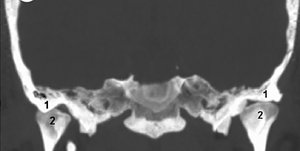

FIG 2 Coronal CT; 1: fossa, 2: condyle.

Computerized Tomography: CT examination of the TMJ should demonstrate the bony cortex, the size and shape of the condyles and their position in the fossa, the joint spaces and centric relation loading zone (a dental term meaning that the condyle is most comfortable in the posterior location of the mandible when it is manipulated gently backward and upward into a retrusive position).8 (Figs. 2-3)